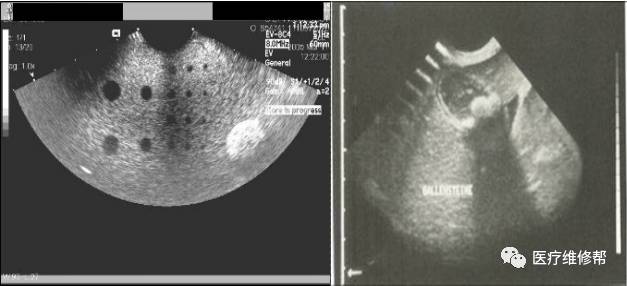

如下图,就是利用专门的工装,从电脑上形象直观的可以看出电容的幅值大小。

图中为109损坏,138、139因老化而容值过大。